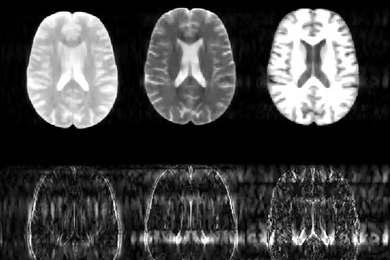

New algorithm could substantially speed up MRI scans

Faster scans could reduce the time patients spend in the machine from 45 to 15 minutes.